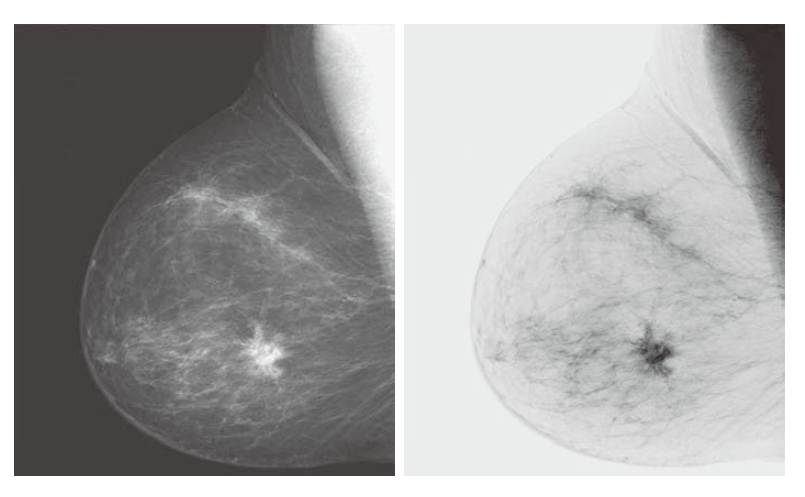

以这种方式反转数字图像的强度级别会产生与照片底片 (photographic negative)相同的效果。**例如,这种处理可用于增强嵌入在图像暗区中的白色或灰色细节,尤其是当黑色区域占主导地位时。**图 3.4 显示了一个例子。原始图像是显示小病变的数字乳房 X 光检查。尽管两幅图像中的视觉内容相同,但一些观众发现使用底片更容易分析乳房组织的精细细节。

--------------------------图3.4:(a)数字乳房 X 光检查。(b)使用公式 (3-3) 获得的底片。(图片 (a) 由通用电气医疗系统提供。)-----------------------------------